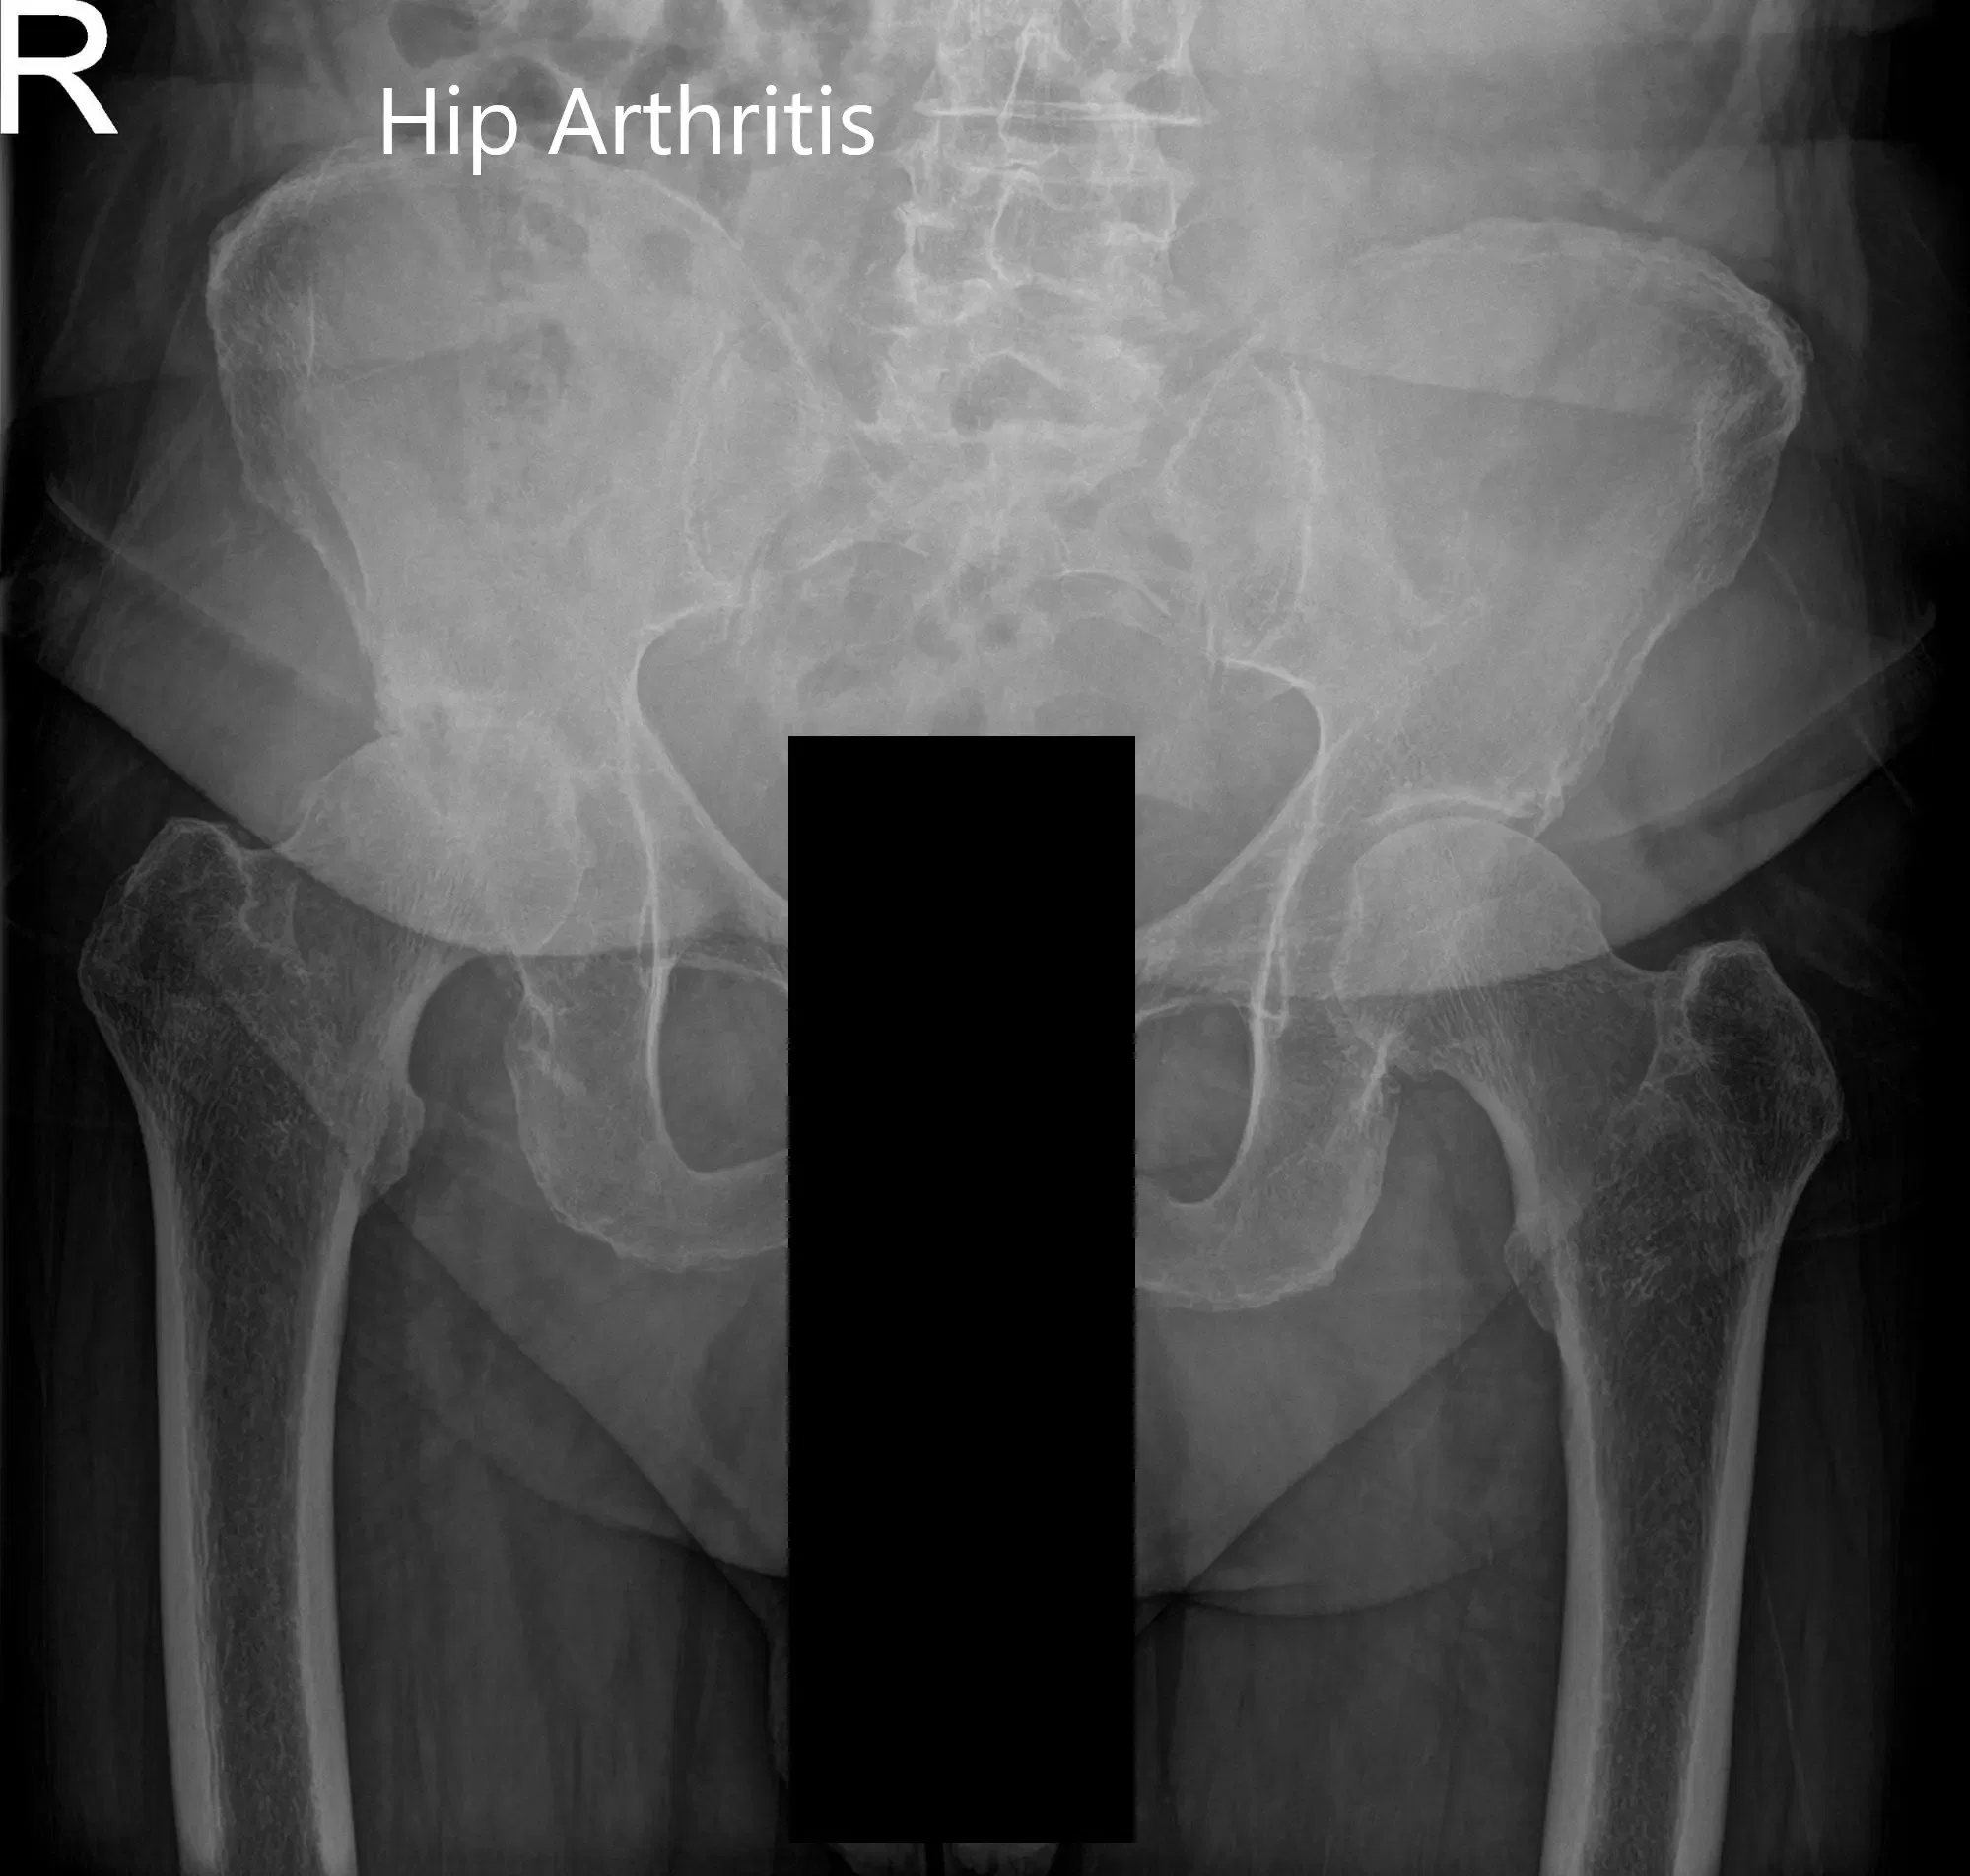

Radiografía preoperatoria de la pelvis, vista AP y vista lateral de la cadera derecha con patas de rana.

Radiografía preoperatoria de la vista AP de la pelvis y vista lateral con patas de rana de la cadera derecha (imagen 2)

El estudio de imagen reveló degeneración osteoartrítica de la cadera derecha. Tras tener en cuenta sus comorbilidades y el dolor limitante del estilo de vida en la cadera derecha, le recomendaron una prótesis total de cadera correcta. Se discutieron extensamente con ella riesgos, beneficios y alternativas. Ella aceptó seguir adelante con el procedimiento tras la autorización médica.